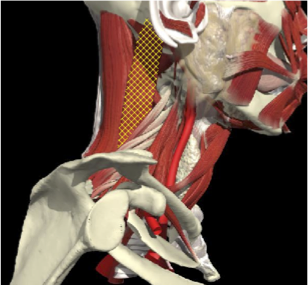

GENERAL PRINCIPLES- CO-CONTRACTION

Voluntary movement is affected by co-contracting muscle pairs. It is important to assess range of individual neck movements but also the effort required and the localisation of pain associated with the movement.

In this patient there is co-contraction of ipsilateral Trapezius and Levator scapulae on the left, restricting rotation to the left and causing local pain

ACCURACY OF LOCALIZATION - SCALENES

ACCURACY OF LOCALIZATION LEVATOR SCAPULAE

LOCALIZATION OF MUSCLES IN DEEPER LAYERS